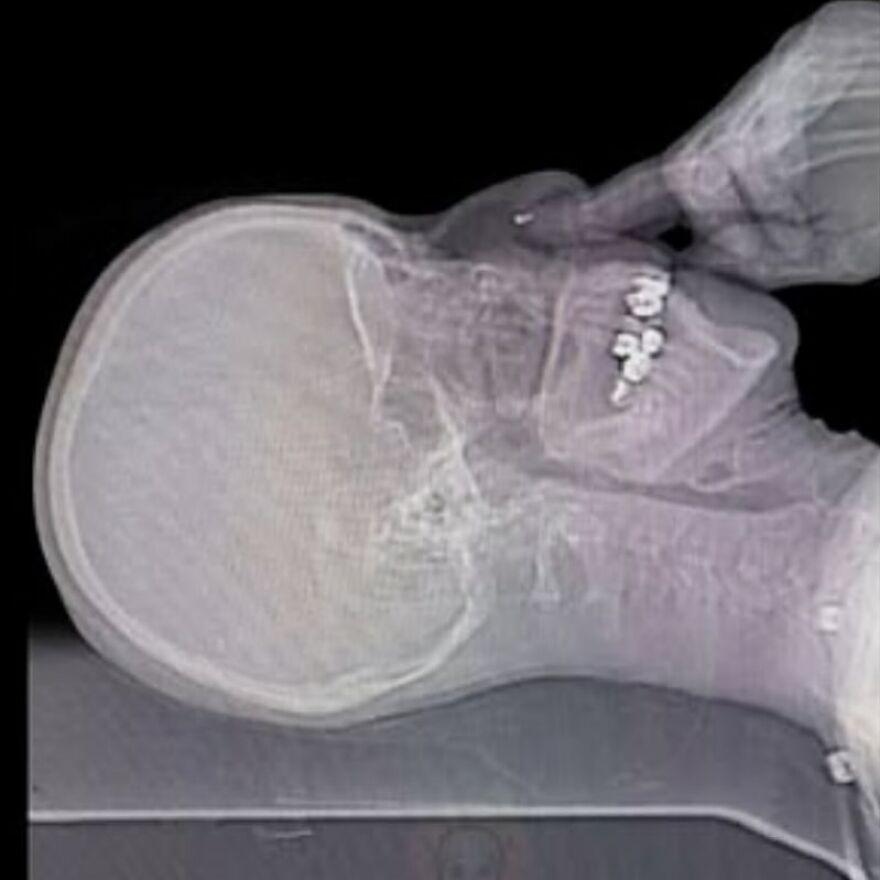

Plain radiograph of wrist joint shows polydactyly with duplication of ulna, duplication of ulnar side of carpal bones, metacarpals and phalanges, absence of radius and absence of thumb. Eight triphalangeal digits are seen. The middle phalanx of medial index finger is hypoplastic